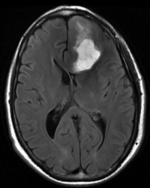

Registration Results

DTI aligned with T1Gd DTI aligned with T1Gd